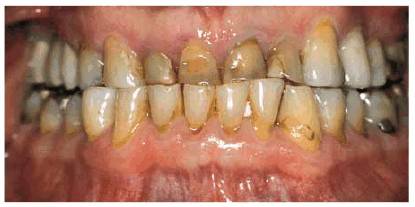

Bruxism can lead to extreme loss of occlusal and incisal tooth structure (Figures 17-11A

to C 17-11D and E 17-11F to H 17-11I and J). For example, a young woman was

Figure 17-11A to C: This case illustrates the severe damage that can be caused by bruxism. The patient is a 56-year-old male who reports that his wife tells him he grinds his teeth while she is trying to sleep. He is also a farmer and is exposed to dust for extended periods of time for much of the year. The combined bruxism and environmental factors have likely contributed to the extreme wear present. As is most commonly seen with cases in which the wear progresses slowly, there has been no discernible loss of vertical dimension, as evidenced by lip position and speech patterns. Note the traumatic occlusal relationship when the patient is in complete intercuspation (A). Views of the severe wear of the maxillary and mandibular arches. Note the calcified, exposed pulp chambers and caries (B and C).